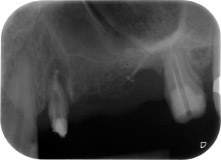

Fig. 1 : Patiente de 58 ans. Radio pré-opératoire montrant une lésion du parodonte apical à la dent 24 et une perte horizontale d'os alvéolaire dans le deuxième quadrant.

Une patiente de 58 ans se plaignait de douleurs et d'une mobilité accrue de la dent pilier 24 de son bridge. Présence d'une inflammation parodontale avec formation de poches de 7 mm de profondeur dans le sens mésiobuccal et de plus de 12 mm dans le sens distal, ainsi que d'une atteinte de la furcation au troisième degré. La radiographie a par ailleurs révélé une lésion parodontale étendue autour de la région apicale de la dent 24 ayant préalablement reçu un traitement endodontique (alio loco) (Fig. 1).